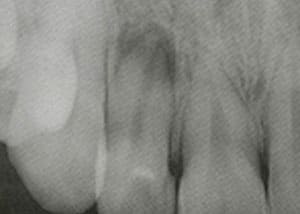

①根尖由来による歯周膿瘍

何らかの原因(熱・酸・力)で歯の神経が死んでしまったとき、根の治療(根管治療)を途中でやめてしまった場合または予後不良の場合に起こることがあります。